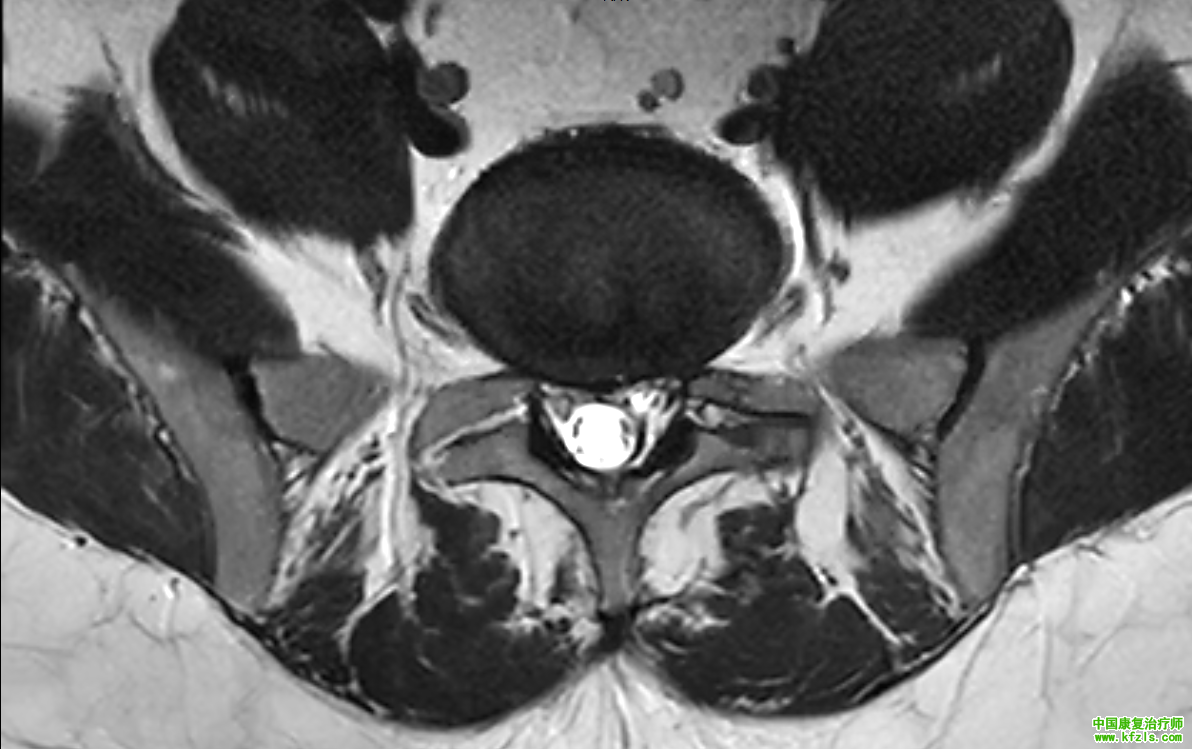

一位34岁绘画老师,男性,主诉是腰部疼痛,伴随右侧放射性麻木到大腿,长时间坐着酸胀感增加,无法搬重物,弯腰疼痛。医院拍片发现双侧椎间孔狭窄,L4/L5,L5/S1椎间盘突出,卡压神经根。直腿抬高试验阳性,slump试验阳性,弯腰测试阳性。

f4940fd6cb609653082a80c604d593b3.png

a00343da74c7834a7b73f62d4cb96ae3.png

3fbf834e35c48b70b4481a499a228fa5.png

*根据以上症状,我们给出了具体康复治疗方案